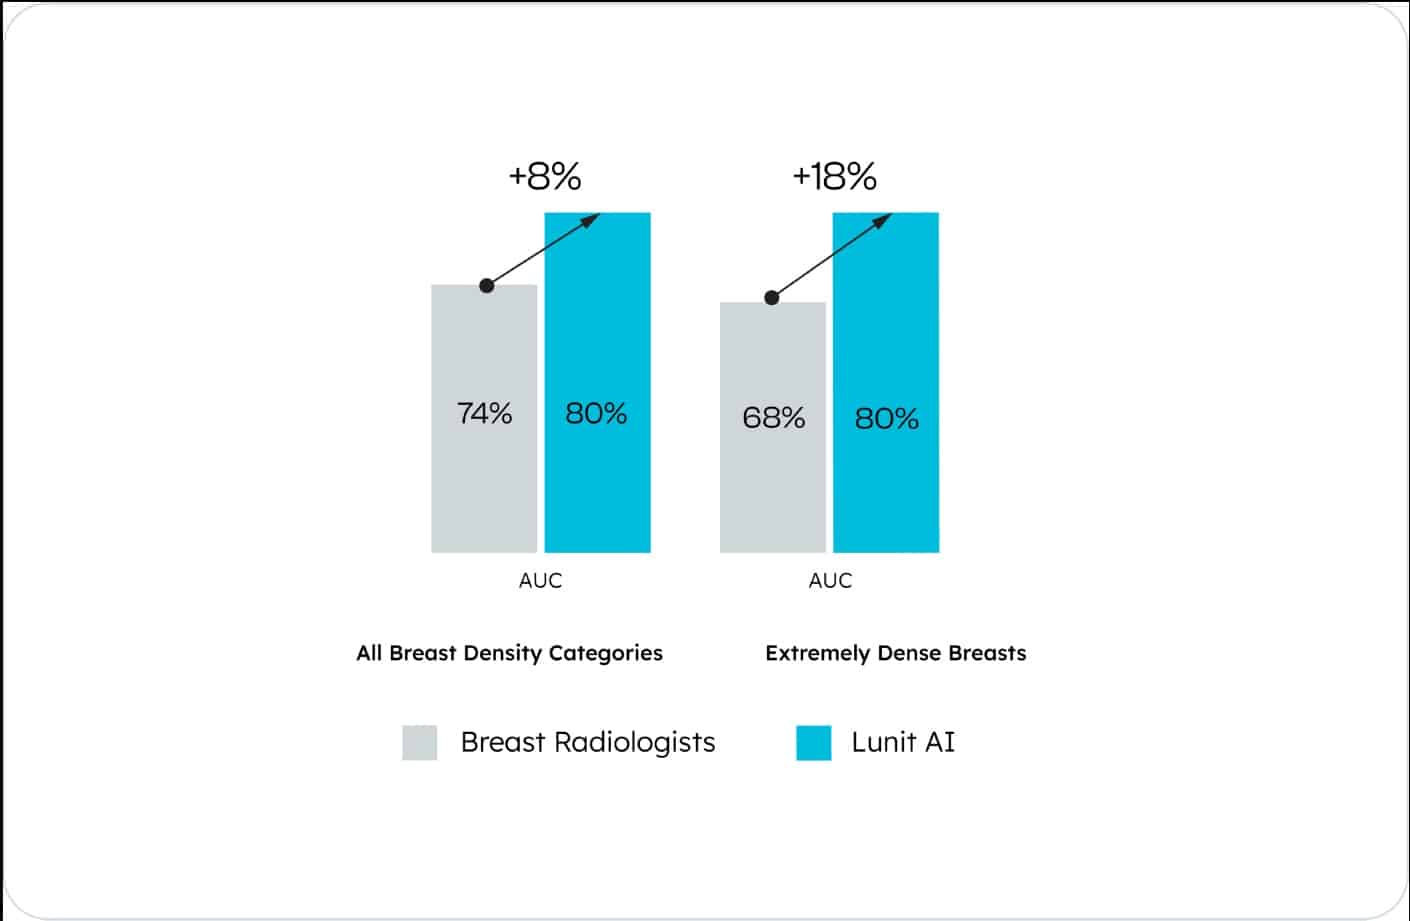

Lunit INSIGHT MMG has an 18% higher accuracy in extremely dense breasts and an 8% higher accuracy in all breast density categories, enhancing detection across tissue types*.

*Kwon, Mr., Chang, Y., Ham, SY. et al. Screening mammography performance according to breast density: a comparison between radiologists versus standalone intelligence detection. Breast Cancer Res 26, 68 (2024).